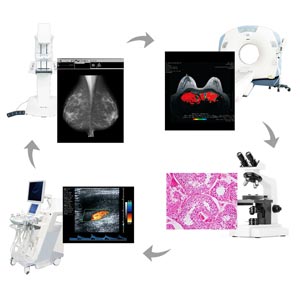

Nella prevenzione del tumore al seno per donne che presentano tessuto mammario denso, vengono sempre più spesso abbinate diverse tecnologie diagnostiche come la mammografia e l'ecografia in combinazione. Nel caso di risultati anomali, seguiranno altre indagini come una biopsia o altre modalità di indagine come risonanza magnetica (RM) o tomografia assiale computerizzata (TAC) che richiedono tuttavia l'impiego complementare di un monitor a colori. RadiForce RX560 è il primo monitor medicale a colori al mondo che integra al suo interno la tecnologia poli- silicone LCD LTPS (Low Temperature Polysilicon), in grado di garantire l'elevatissima luminosità richiesta per l'impiego nel campo senologico e finora raggiunta solamente dai monitor a scala di grigio. il monitor RadiForce RX560 fornisce una luminosità pari a 1100 cd/mq. In tal modo, il display restituisce con l amassima precisione e accuratezza sia immagini a colori provenienti da esami diagnostici (come l'ecografia o referti istologici) che da tecniche di imaging mammografiche in scala di grigi. L'elevato rapporto di contrasto di 1500:1 si avvicina molto alle caratteristiche dei monitor monocromatici, le tonalità del nero vengono visualizzate senza presentare alcun effetto "slavato".

Eizo RadiForce RX560 dispone della tecnologia Hybrid Gamma PXL che identifica automaticamente su unico schermo immagini in scala di grigio e a colori, impostando la luminosità ideale. Ciò garantisce un altissimo livello di sensibilità diagnostica di immagini in scala di grigio e a colori. Il modello RX560 è in grado di restituire contemporaneamente immagini in scala di grigio o a colori, provenienti da sistemi di acquisizione diagnostici come TC mammografica, mammografia, CT, RM, ecografia o da esiti istologici e grazie alla sua flessibilità trova dunque largo impiego nella pratica clinica quotidiana.